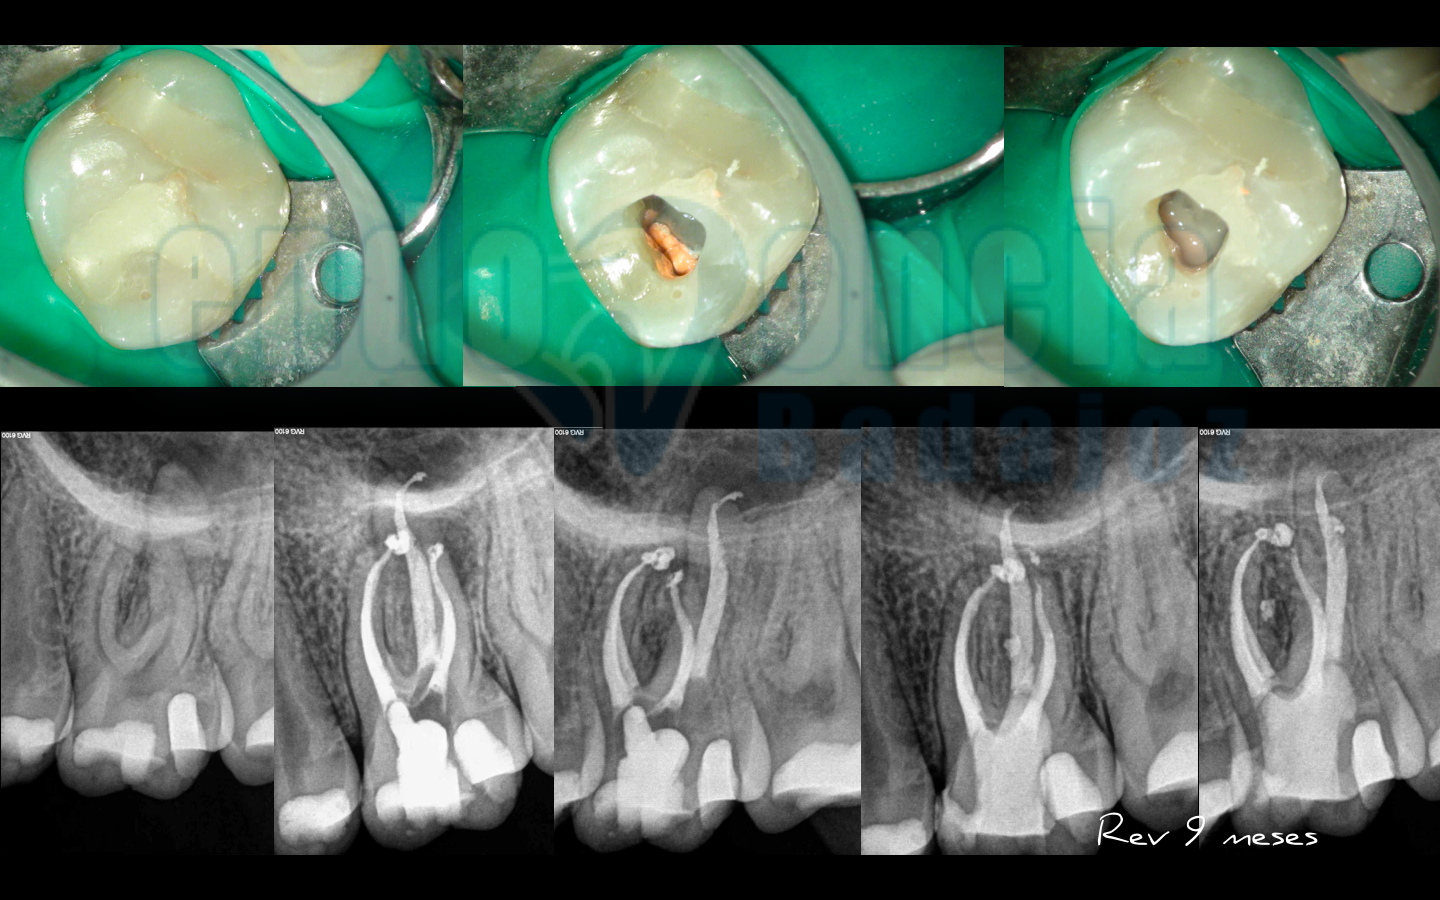

Caso 2:

Premolar superior, con un tratamiento endodóntico con perno y suboturación que presentaba una lesión apical. Retratamos la pieza y vemos como a los 10 meses existe una buena regeneración apical.